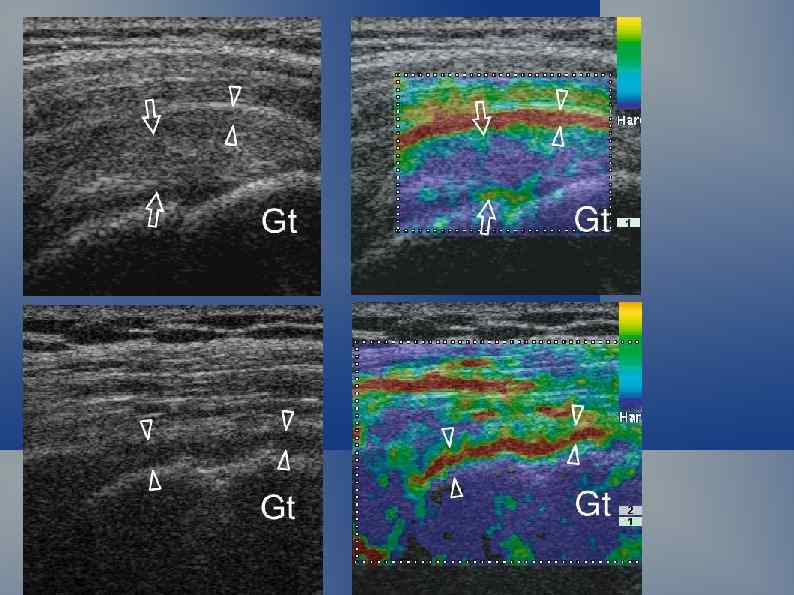

Надколенник Киста жирового тела Гофа В исследовании мышечноскелетной системы действуют те же физические принципы. Акустически плотные структуры (камни, кости, металлические предметы) полностью отражают звуковую волну. Ограниченное скопление жидкости формирует дистальное усиление эхосигнала.

Реверберация. Эпифиз локтевой кости. Эффект анизотропии у сухожилий